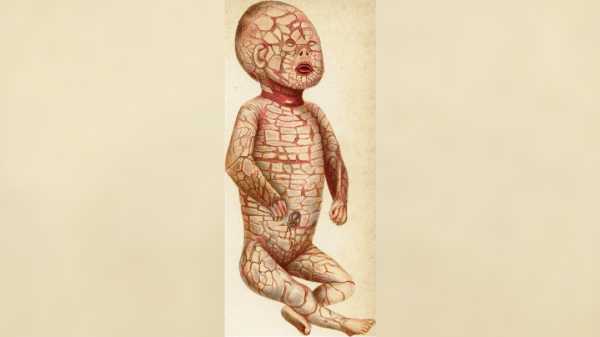

Немовлята, народжені з іхтіозом арлекіна, мають дуже характерні риси, зокрема пластинчасті лусочки шкіри з глибокими тріщинами між ними. (Зображення: J. Bland Sutton — A Case of General Seborrhoea or “Harlequin” Fœtus J. Bland Sutton Med Chir Trans. 1886; 69: 291–296.1. PMCID: 2121560, Public Domain, Link)

Симптоми: Транспортування молекул жиру в епідермісі важливе для підтримки зволоження шкіри, а також необхідне для її правильного розвитку в утробі матері та після народження. Коли у дітей білки ABCA12 занадто короткі або повністю відсутні, ці діти народжуються з товстими, пластинчастими лусочками шкіри, через що шкіра дуже щільно розтягується.

Щільна шкіра легко тріскається, утворюючи тріщини. Напруга тягне повіки та губи ураженої дитини, вивертаючи їх навиворіт, а також стискає рухи грудної клітки, що перешкоджає диханню та прийому їжі. Також поширеним є поганий ріст нігтів та волосся.

Діти з іхтіозом арлекіна часто народжуються передчасно, і вони також можуть проявляти додаткові симптоми та ознаки, такі як плоский ніс, порушення слуху, вуха, зрощені з головою, набряклі руки та ноги, а також знижена рухливість суглобів.

Цей стан порушує захисний бар'єр шкіри, роблячи немовля вразливим до зневоднення та нездатним регулювати температуру тіла чи добре боротися з інфекціями. У немовлят, які переживають період новонародженості, «бронеподібні» пластинки з часом відшаровуються, а решта шкіри стає дуже червоною, сухою та лускатою.